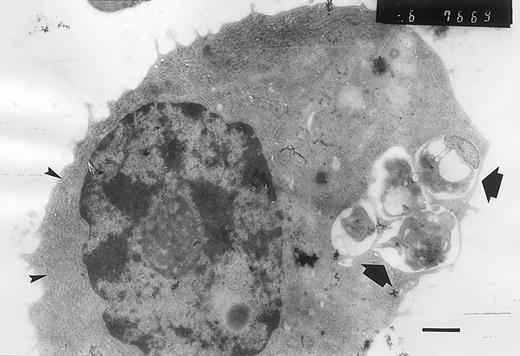

Atypical plasma cell containing phagocytic vacuoles.

The phagocytic vacuoles are indicated by arrows, and the large amount of rough endoplasmic reticulum, by arrowheads. There is a nuclear chromatin typically resembling the appearance of a “cartwheel” (bar = 1 μm).